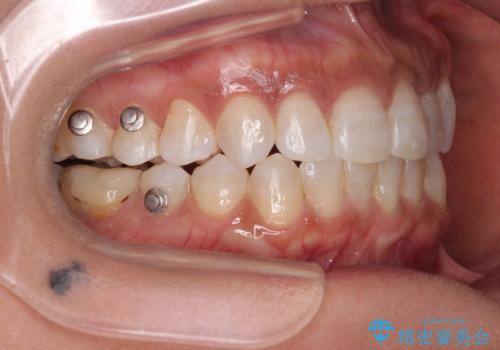

咬合力による臼歯離開は顎間ゴムで改善されましたが、それとは別に下顎小臼歯がマウスピースに追従せず、補正のためのゴムかけが必要となりました。

大変なゴムかけ作業を頑張っていただき、無事に治療を終えることができました。